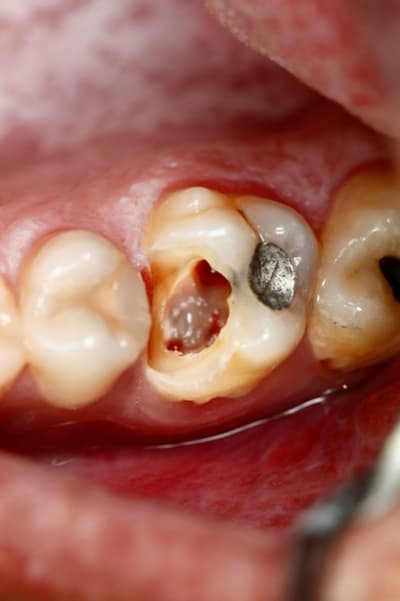

Si dés le départ on décide de faire l'endo et couronne, on taille, on ouvre, et a la fin on se dit qu'on a bien fait de faire la couronne, vu qu'il reste pas grand chose. Au passage on perd beaucoup de résistance mécanique de la dent, et on descend toute les limites au niveau gingival ce qui dans le temps expose la limite à une contamination biologique, reprise de carie ...etc...

Ici, je fais l'endo en essayant de garder ce que je peux de la dent...

Ensuite a la fin de l'endo, c'est propre, j'ai un accès étanche, j'en profite pour coller et remonter la limite. C'est le meilleur moment pour le faire, non ? ... Et surement le meilleur moyen d'avoir une étanchéité sur la zone faible de cette dent, sa limite proximale infra gingival.